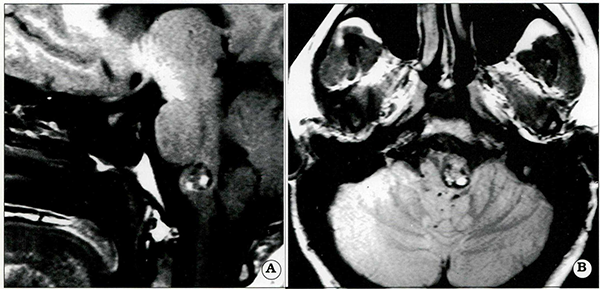

La elección del abordaje quirúrgico depende de la localización de la lesión, Es importante efectuar cuidadosamente un plan quirúrgico que permita un abordaje apropiado con mínima morbilidad. Las lesiones de la superficie anterolateral de los pedúnculos cerebrales (Fig, 2) y región de la cisterna interpeduncular pueden ser abordadas a través de un abordaje pterional transilviano o subtemporal, En contraposición, lesiones más inferiores ubicadas en la superficie anterolateral de la protuberancia anular son difíciles de abordar por la vía subtemporal clásica (Fig. 3), El uso de abordajes de base de cráneo, como por ejemplo el abordaje subtemporal transpetroso posterior, presigmoideoretrolaberíntico, transigmoideo, o sus combinaciones, permite una exposición más apropiada a esta región anatómica. Estos abordajes se efectúan con el paciente en posición supina, con un rollo por debajo del hombro y la cabeza rotada hacia el lado opuesto a la lesión, La elección y agresividad de estos abordajes debe basarse en el tamaño y características particulares de cada caso. Las lesiones ubicadas en la región pineal, superficie dorsal de los pedúnculos cerebrales, velo medular superior y pedúnculos cerebelosos superiores pueden ser resecadas por vía infratentorial supracerebelosa. Este abordaje puede ser efectuado en posición prono, semisentado, o posición 3/4 prono.

Fig. 2

. Paciente femenina de 30 años que presentó cefaleas intensas y hemiparesia progresiva izquierda. Vistas axial (A) y coronales (13) demuestran una lesión del pedúnculo cerebral derecho, La lesión fue abordada por vía subtemporal derecha con resección completa de la lesión. La paciente mejoró clínicamente en el período postoperatorio inmediato.